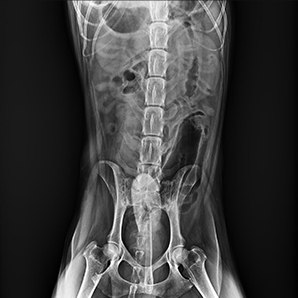

Get a high-quality instant image

Instant images on the tube head allow faster diagnoses and enable better communication with animal owners intuitively and clearly.